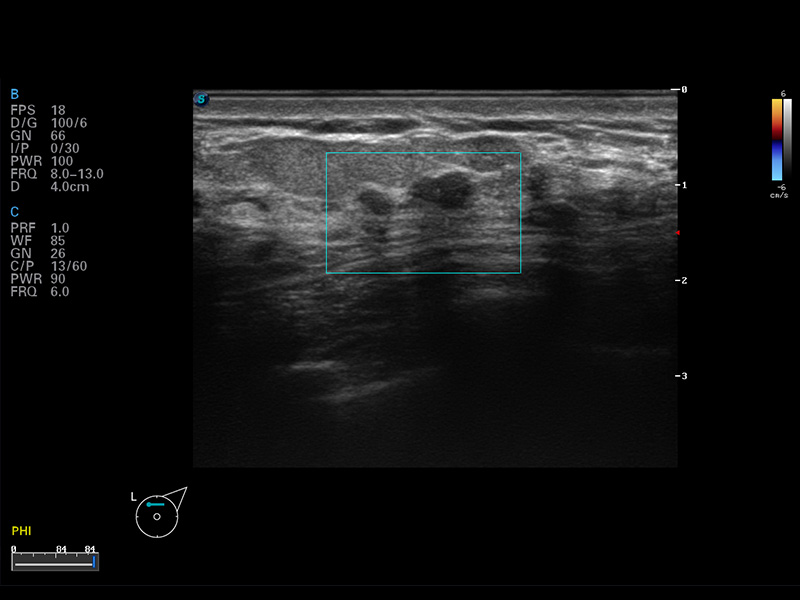

S8 EXP便携式彩色多普勒超声诊断仪是哈哈体育官网研发的高端全身应用型便携彩超。高通道的VIS平台融合可视化(Visual)、智能化(Intelligent)和人性化(Smart)的特点,配以哈哈体育官网自主研发生产的探头大家族,使您能够快速、准确的获得病人信息,提高工作效率的同时减轻疲劳。

谐波成像

空间复合成像